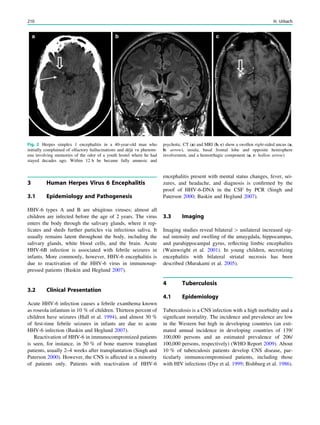

Fig. 2 Dural a. v. fistula. A 53-year-old man presented with two tonic–

clonic seizures. MRI shows circumscribed edema in the left frontal lobe

(a, hollow arrow) and an abnormal vessel running in the left sulcus

rectus (c, arrow). The digital subtraction angiogram of the left internal

carotid artery shows a frontobasal dural arteriovenous fistula fed via

ethmoidal arteries (d, arrow) and confirms the abnormal vessel as a

draining vein (e, arrow)